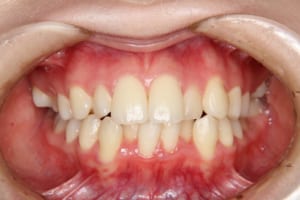

• After

治療後

治療期間 4年6か月

費用(保定除く) 889,550円(税込)

顎間ゴムも頑張ってくれたが期間がかかりました。

いずれ牽引した犬歯の再度の補綴処置を予定しています。